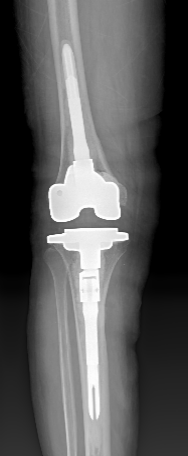

关节外科/运动医学科赵良军副院长、覃刚主任手术团队联合手术室、检验科及临床药学部等MDT团队为患者制定了周密的治疗方案,术前相关检查无明显手术禁忌症,在全麻下顺利完成右侧人工全膝关节表面置换术后感染清创、假体取出、新的假体按装等一期翻修手术。该手术在我院的成功开展,为髋膝关节置换术后感染患者提供了一套新的手术治疗方案。

图5 术后